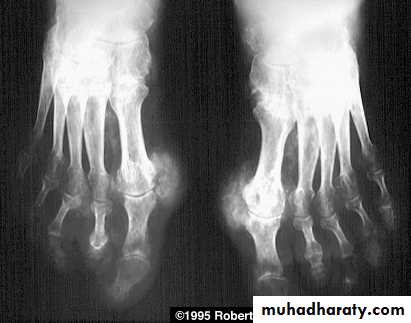

RHEUMATOID ARTHRITISFema1e:male = 3:lRadiographic features

Early changes

* Peri articular soft tissue swelling (edema, synovial congestion)

*Peri articular osteoporosis in symmetrical distribution (hallmark)

* Preferred sites of early involvement

Hands: 2nd and 3rd MCP joint

Feet: 4th and 5th MTP joint

Late changes

*Erosions (pannus formation, granulation tissue) first attack joint portions in which protective cartilage is absent (i.e., capsular insertion site).

* Erosions of the ulnar styloid and triquetrum are characteristic.

Subluxations , Carpal instability and ulnar deviation .

* Fibrous ankylosis is a late finding.

• Rheumatoid arthritis. Bilateral changes are fairly symmetrical. Soft-tissue swelling is demonstrated, especially over the ulnar styloids. Erosions are demonstrated at the carpus, distal radius and ulna, with joint space narrowing and collapse of bone. Metacarpophalangeal erosions are also seen associated with joint space narrowing. There is a swan-neck deformity of the right fifth distal interphalangeal joint